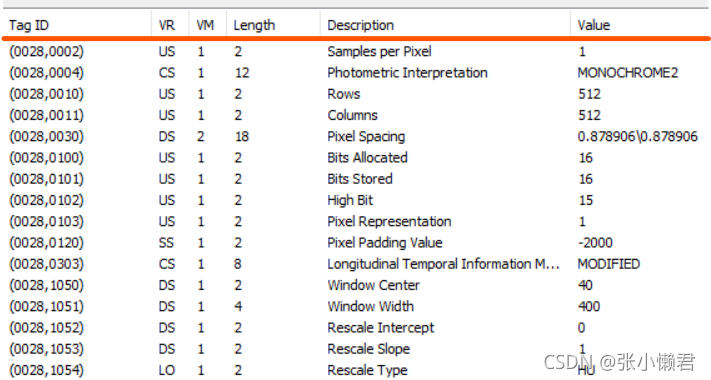

点击 “A”标志的下拉按钮,点击“ show DICOM tag”

0028组描述图像信息参数,上图的表格就是Tag组号0028的数据元信息。

Tag号:0002,0010,决定数据元素的传输方式,VR是显式还是隐式。

Tag号:7fe0,0010对应像素数据开始的地方。

②值类型VR:2字节字符串,是数据元素的数据类型。VR有27种

③数据值长度L:2字节或4字节无符号整数,具体长度取决于传输语法,表示数值的长度。

④值域VF:表明数据元素的值。